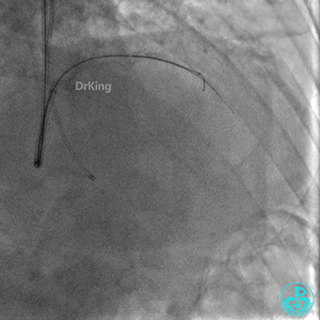

启动Reverse CART,正向2.0×15mm球囊扩张后逆向导丝尝试进入前降支近端真腔。